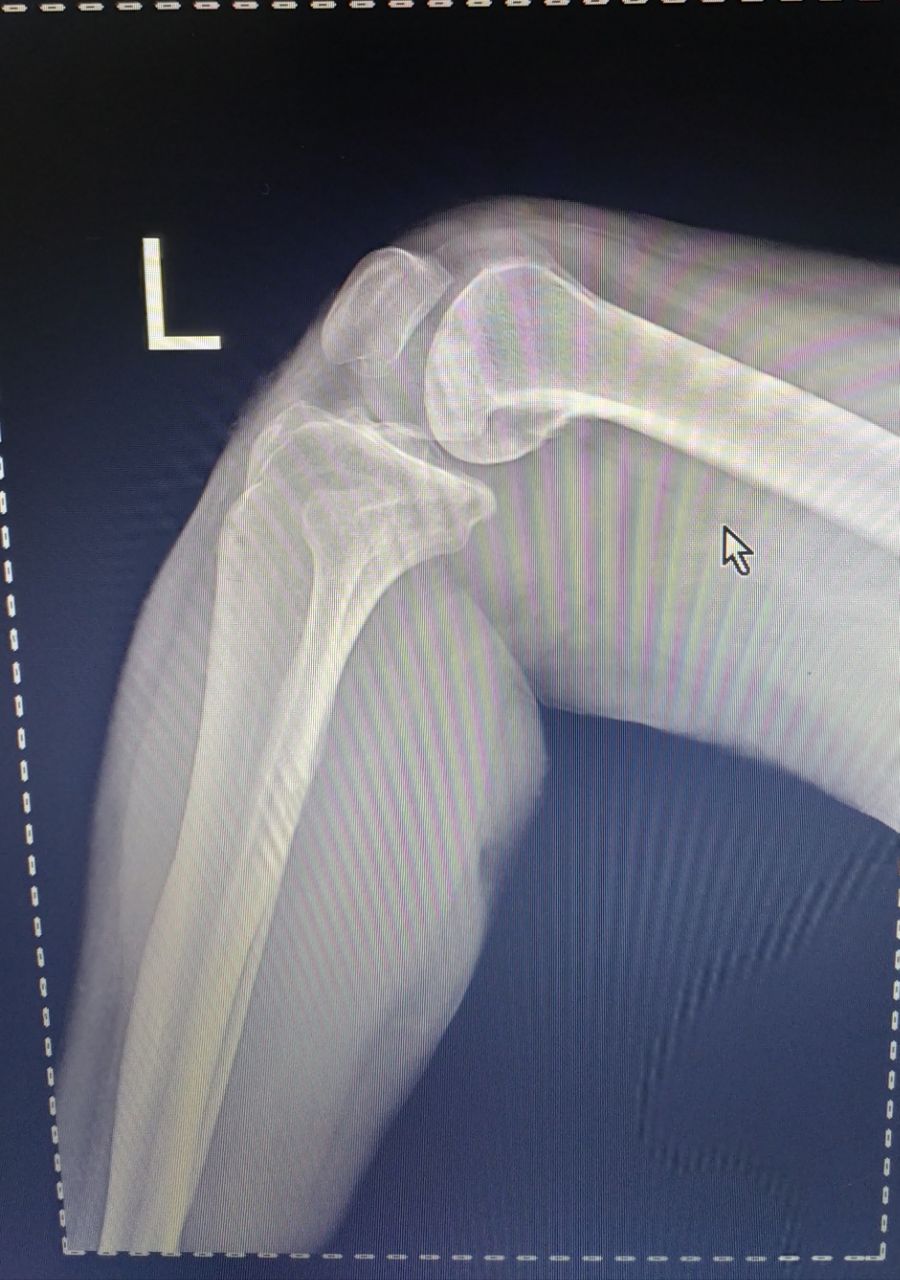

Коллеги! Хотелось бы услышать Ваше мнение по следующим снимкам. (P.S. за качество извиняюсь.)

Пустая амбулаторная карта. Мужчина 1979г.р.